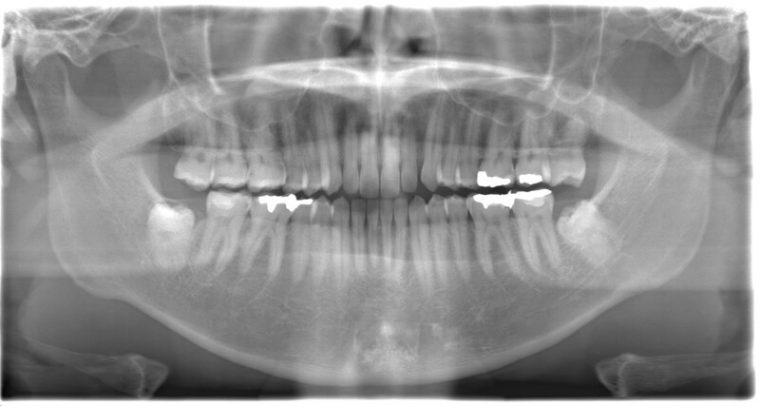

CASE 1

| 年齢・性別 | 30代・女性 |

| 主訴 | 左右に分けて親知らずを抜きたい、できれば痛くなく抜きたい |

| 親知らずのはえ方 | 完全に出ていてまっすぐはえている |

| 抜歯期間 | 15分 |

| 抜歯費用 | 約2,000円(保険内) |

| 抜歯内容 |

何度か虫歯になり痛みはないが早めに抜きたい。 完全に頭が出ているため歯ぐきを切ったり骨を削らずに抜歯しました。 根の形も単純なため抜歯自体は5分もかからず上下ともに終わりました。 術後痛みや腫れも出ていません。 抜歯後は感染をしやすいため必ず抗生物質を飲み切ってください。 |